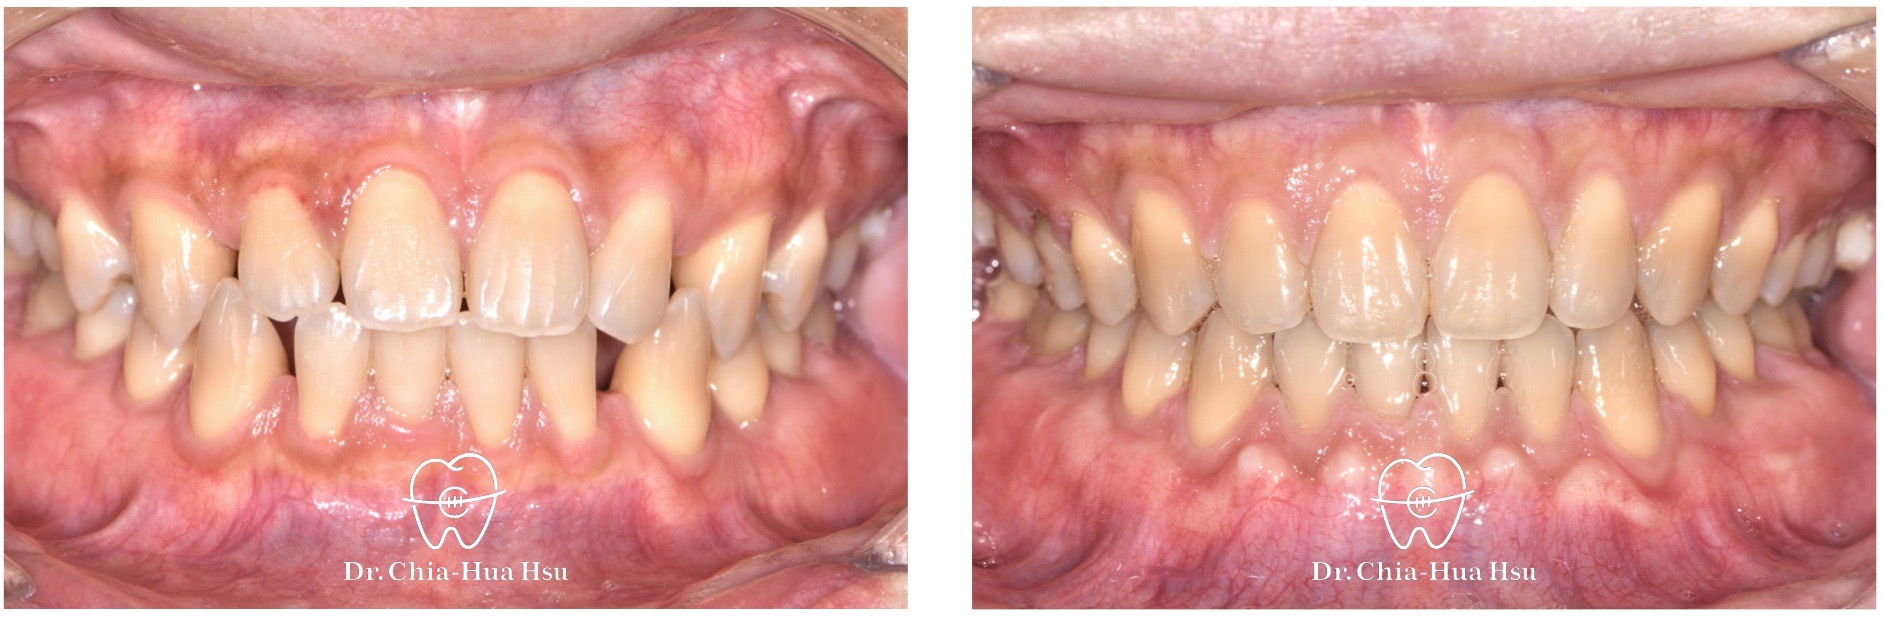

治療中

• 治療過程:治療過程中,下顎使用矯正暫時迷你骨釘 (TADs)、槓桿臂 (Lever arm) 與橡皮鏈 (Power chain),將後牙往前拉並關閉縫隙。

• 矯正小知識:懸臂 (Cantilever arm) 是一段由金屬絲 (多為不鏽鋼或鈦合金) 製作的細長結構,通常一端是固定在支點(Anchor tooth 或骨釘),另一端是自由懸空,藉由橡皮鏈、彈力線等方式,施力於目標牙齒。